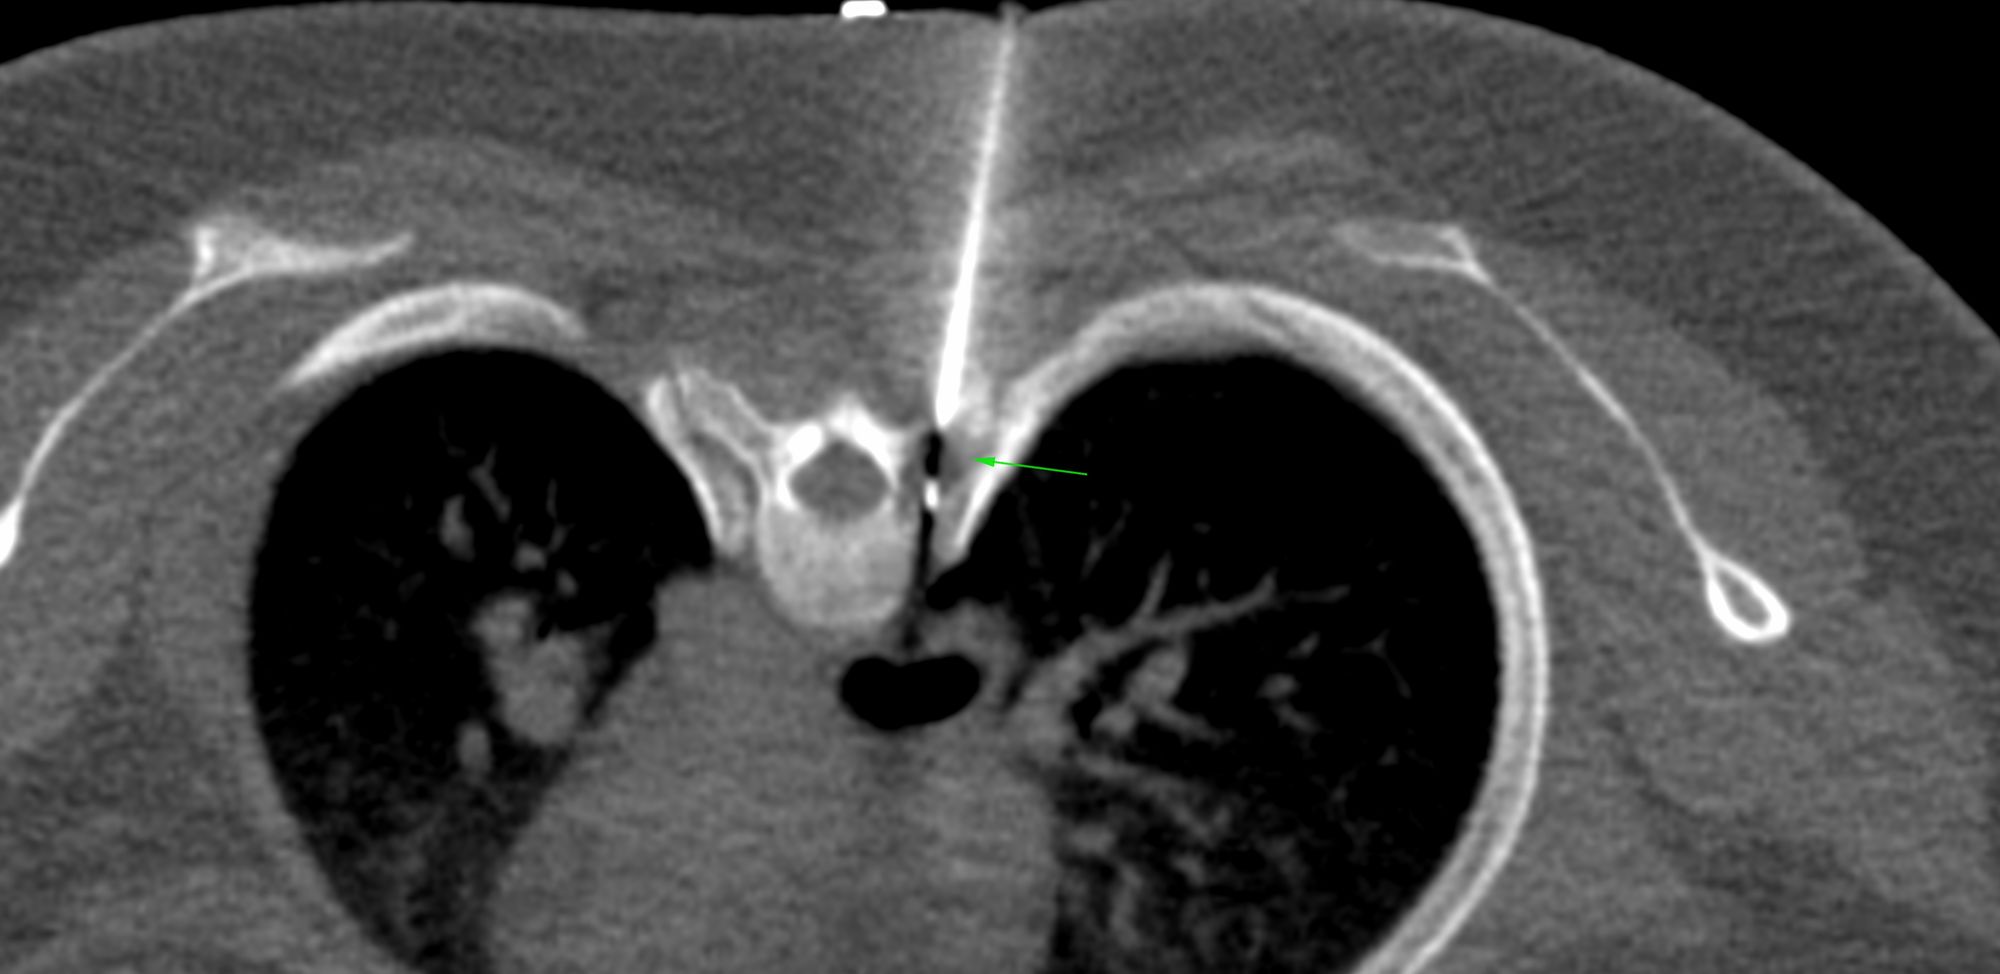

Case 18: Non-Resolving Consolidation Biopsy and Management of Entry Pneumothorax

Bhavin Jankharia - 31 March 2021